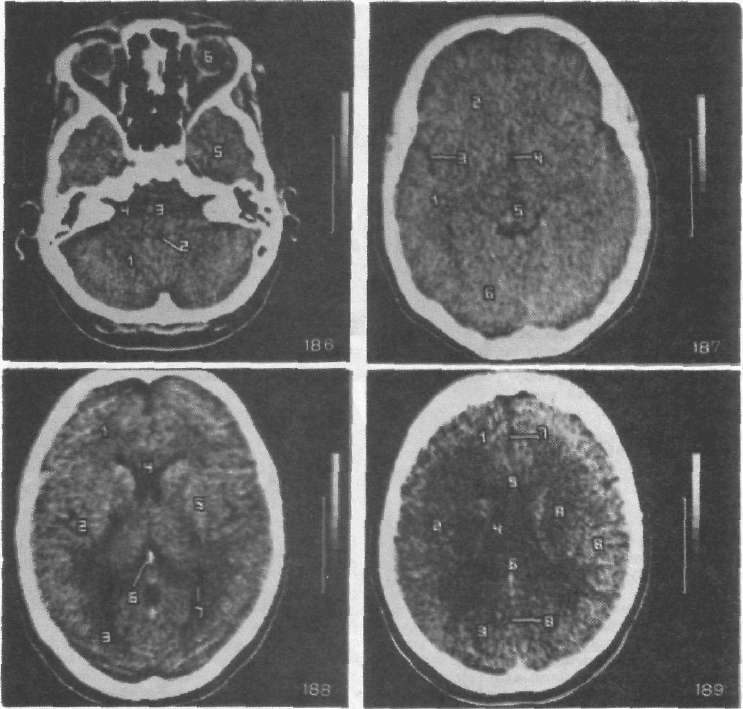

В срезе на уровне среднего мозга (рис. 187) прослеживаются: вещество височных (1)

и лобных (2) долей, латеральные (сильвиевы) борозды мозга (3), III желудочек мозга (4),

средний мозг (5), затылочные доли (6).

Томографический слой на уровне базальных ядер конечного мозга (рис. 188) содержит

изображение вещества лобных (1), височных (2) и затылочных (3) долей, передних рогов

боковых желудочков мозга (4). Здесь же хорошо видны базальные ядра конечного моз-

га (5), шишковидное тело (6) и сосудистые сплетения в задних рогах боковых желудочков

мозга (7).

На уровне тел боковых желудочков мозга (рис. 189) визуализируются белое (А) и се-

рое (В) вещество лобных (1), теменных (2) и затылочных (3) долей, тела боковых желудоч-

ков мозга (4), колено (5) и валик (6) мозолистого тела, передние (7) и задние (8) отделы

серпа мозга.